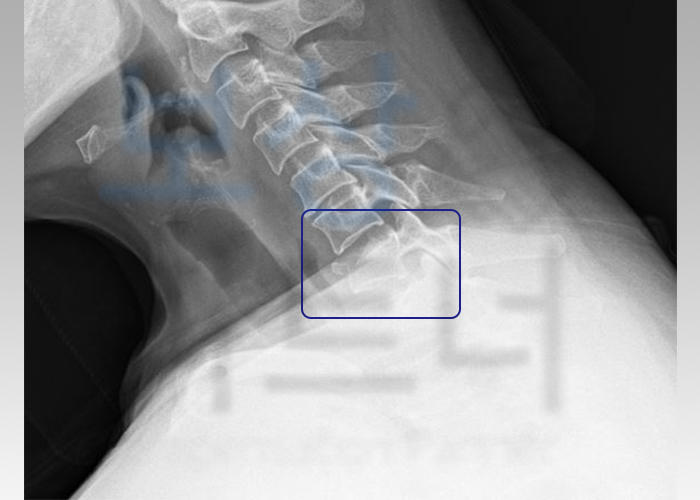

병명: 경추 제7번 방출성 골절 (C7 부위의 골절)

바로 목뼈 중의 가장 아래 부분인 7번 경추 방출성 골절을 당하셨는데요.

척추체에 위아래로 강한 압력으로 인해, 척추가 찌그러지면서 파괴된 골편이 후방으로 돌출되는 골절을 말합니다. 압박골절의 심한 형태가 방출성 골절이라고 보시면 되는데, 경추에 이런 골절이 발생될 경우에는 척수신경의 손상 위험이 있게 됩니다.

- C7 부위의 압박 골절

- 척추(등뼈)에 심한 운동장해를 남긴 때, 40%

(영구장해)